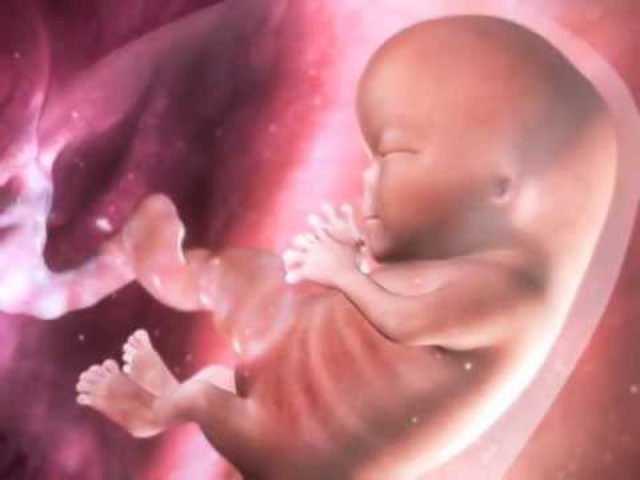

• 12 Semana

12 Semana

El feto mide 9cm y pesa entre 15 y 20 gramos.

Se disminuye su crecimiento, sus extremidades crecen.

Separacion de los dedos en manos y pies

Ademas que aparece el refljo de succion